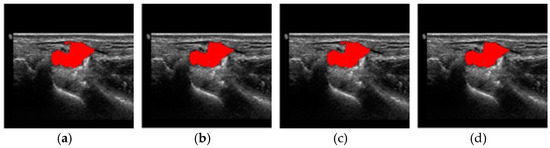

4. Results and Discussion